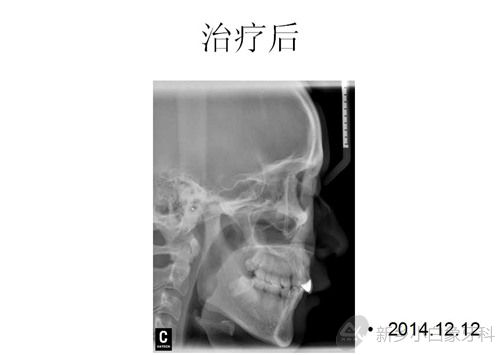

于2014年12月12日治疗结束,患者非常满意。